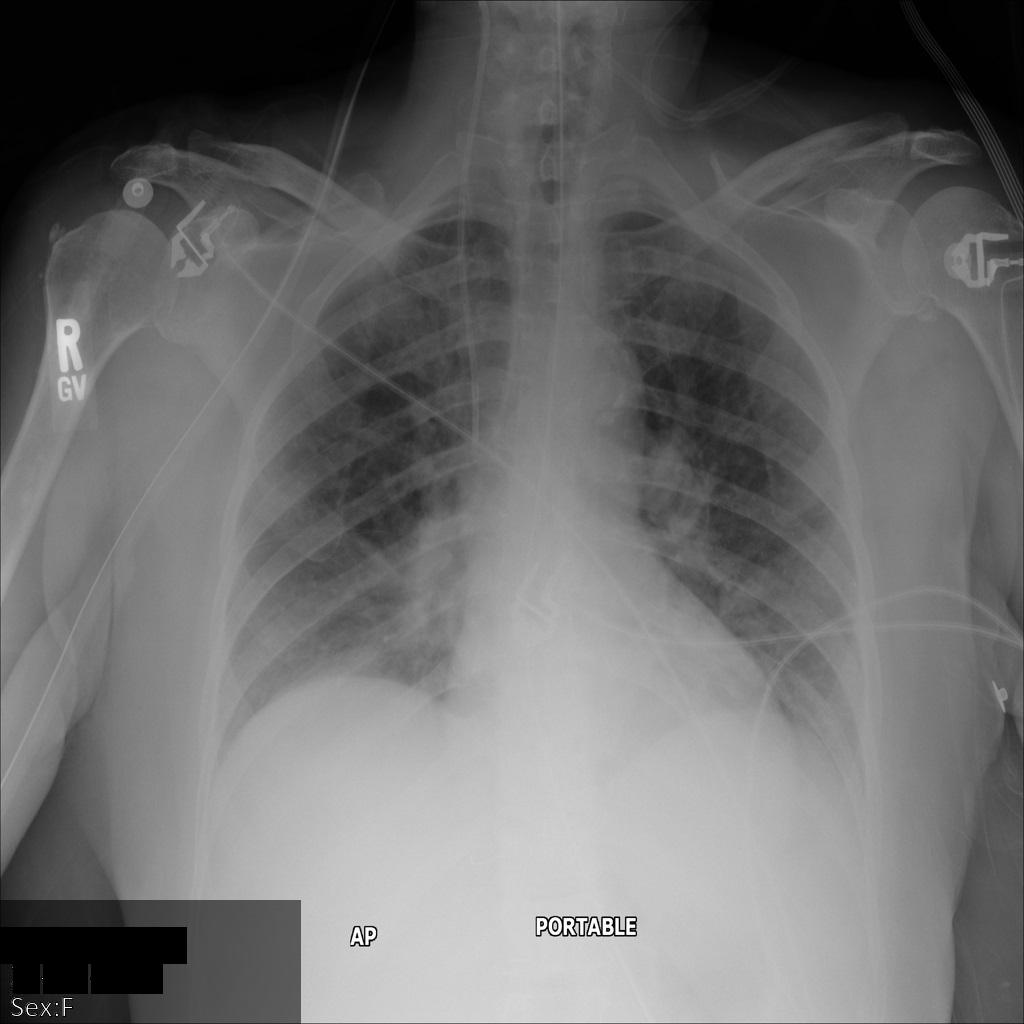

Después de enviar la imagen a la API de Cloud Healthcare mediante la opción REDACT_SENSITIVE_TEXT, la imagen aparece de la siguiente manera:

Puedes ver que ocurrió lo siguiente:

- Se ocultó el elemento

PERSON_NAMEen la esquina inferior izquierda de la imagen - Se ocultó el elemento

DATEen la esquina inferior izquierda de la imagen

El sexo del paciente no se ocultó porque no se considera texto sensible de acuerdo con los Infotipos de DICOM predeterminados.